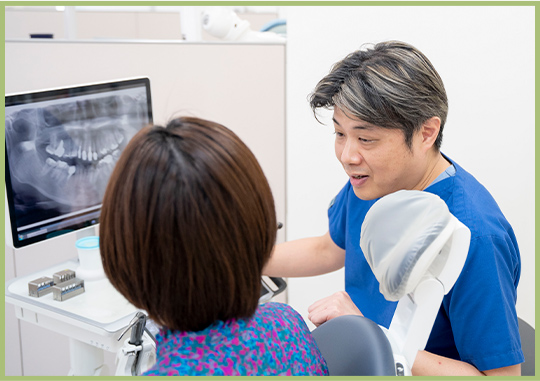

カウンセリングを

大切にした診療

わかりやすい説明

現在のお口の状況や治療内容を患者さまに把握していただくことは、治療中の安心感や、治療後の満足度につながります。そのため当院では視覚的にご理解いただきやすいツールを用いながら、丁寧にわかりやすく説明することを心がけています。

こんな取り組みをしています

治療前・治療後の比較で

治療効果を明確に

口腔内写真・

レントゲン画像で

現状をしっかり把握

患者さまのお声を

大切にしています

カウンセリングの時間をしっかり確保し、患者さまのお悩みやご希望をお伺いします。そのうえで年齢やライフスタイルを考慮した治療をご提案し、ご納得いただいてから治療を開始するようにしています。